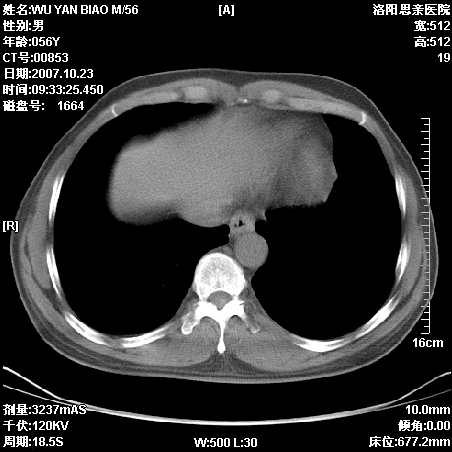

标题: CT10160:M56Y,体检发现,病人无不适,病人随访中

后上纵隔占位,与肺交界清,宽基底附着脊柱,密度均匀,局部骨质无明确改变.

考虑;神经源性肿瘤,---起源交感n链?,不除外肠源性囊肿.

1、病灶在后纵隔脊柱旁沟内,此处是神经原性肿瘤的好发部位

2、病灶边缘光滑整齐,更说明病灶来于纵隔,由于有胸膜的包裹所以才导致这么光滑的边缘

3、病灶内的密度均匀